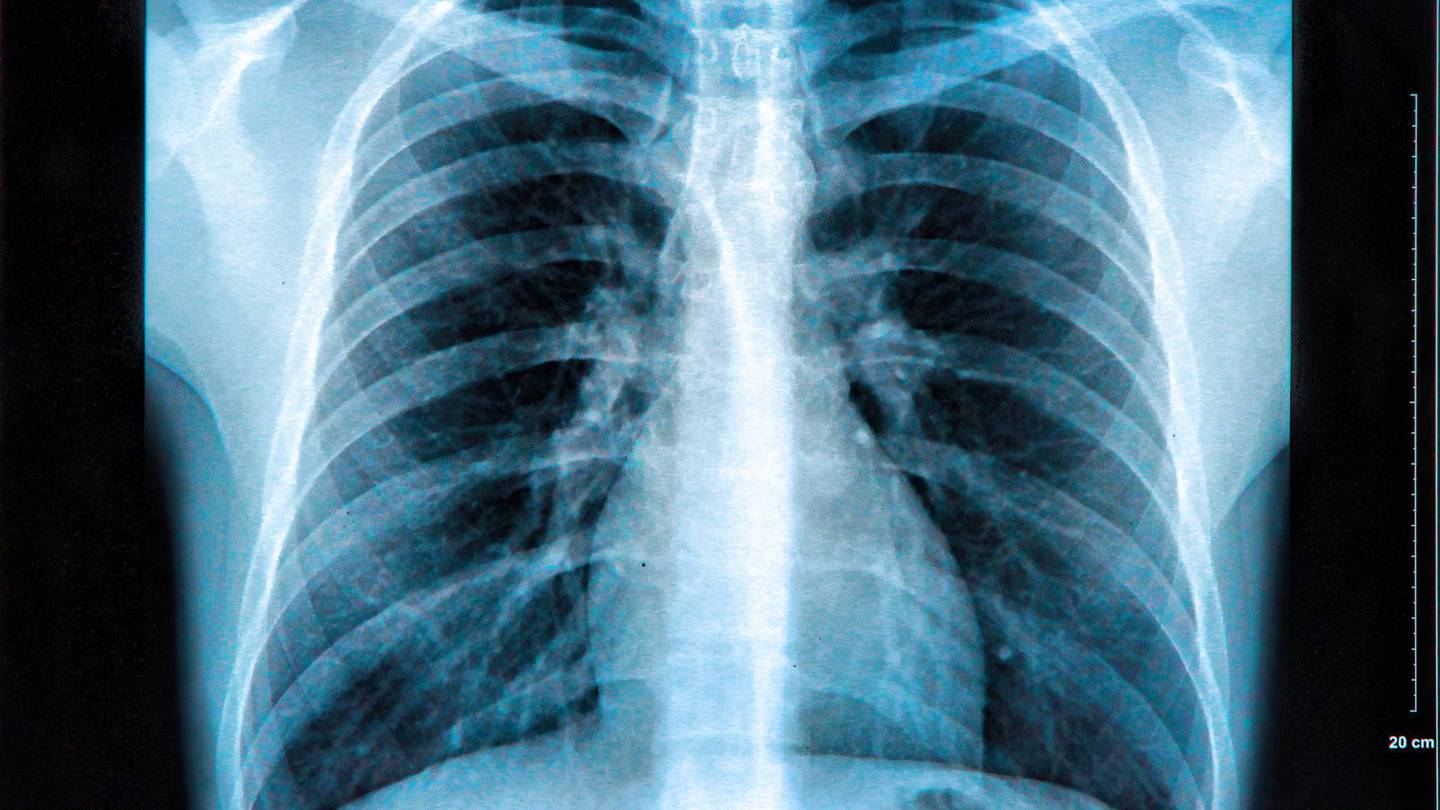

Mini robot detectará cáncer en los pulmones

Dada la importancia de detectar a tiempo el cáncer de pulmón, siendo uno de los más mortales, investigadores trabajan en un robot miniatura que sería capaz de introducirse dentro de los pulmones para verificar el estado en el que se encuentran los mismos.